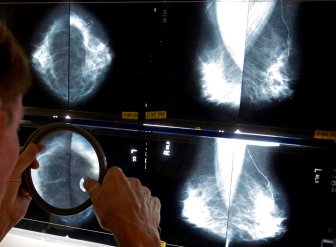

Mammograms

Alberta lowers age for women to be screened for breast cancerAlberta Health Services has lowered the recommended age for biennial breast cancer screening for average-risk women from 50 to 45.HealthOct 18, 2022

Cancer foundations in Saskatchewan launch fundraiser to save the ‘Breast Screening Bus’Since 2002, the Breast Screening Bus provided mammograms for residents in rural and remote communities of Saskatchewan, but funding is now needed for a new bus.HealthOct 3, 2022

15 patients in N.L. require followup as review of thousands of mammograms continuesThe province's health authorities have identified 15 patients this week requiring further followup as a review continues of thousands of mammograms.HealthSep 15, 2022

‘How the hell did this happen?’ More than 16,500 mammograms under review across N.L.Officials from three of the province's four health authorities told reporters the approximately 13,884 mammograms under scrutiny represent about 11,751 patients.HealthAug 31, 2022

Newfoundland health authority reviewing about 3,000 mammograms for possible issuesThe health authority will review its mammogram viewing procedures and look at whether this error occurred because staff had been working from home during the COVID-19 pandemic.HealthAug 24, 2022

Disabled women in Quebec still struggling with mammogram access: advocatesA community group advocating for people with disabilities claims some women are having trouble getting access to mammograms.CanadaMay 4, 2022

AI can spot breast cancer better than humans, study findsArtificial intelligence programs are better at spotting cancer than humans, a new study suggests. What does that mean for cancer detection?HealthJan 1, 2020

Many women aren’t told they have dense breasts. Here’s why it matters43 per cent of women ages 40 to 74 have dense breasts, and they can have serious implications.LifestyleOct 3, 2019

New breast cancer screening guidelines are outdated and dangerous, experts sayMore than 130 breast-cancer doctors and researchers disagree with new screening recommendations, saying the task force is basing their recommendations on outdated data.HealthJan 28, 2019

Patients should decide when to get mammograms: Canadian health expertsNew guidelines from the Canadian task force on preventive health are empowering women to take charge of their health when it comes to breast cancer screening.HealthDec 10, 2018